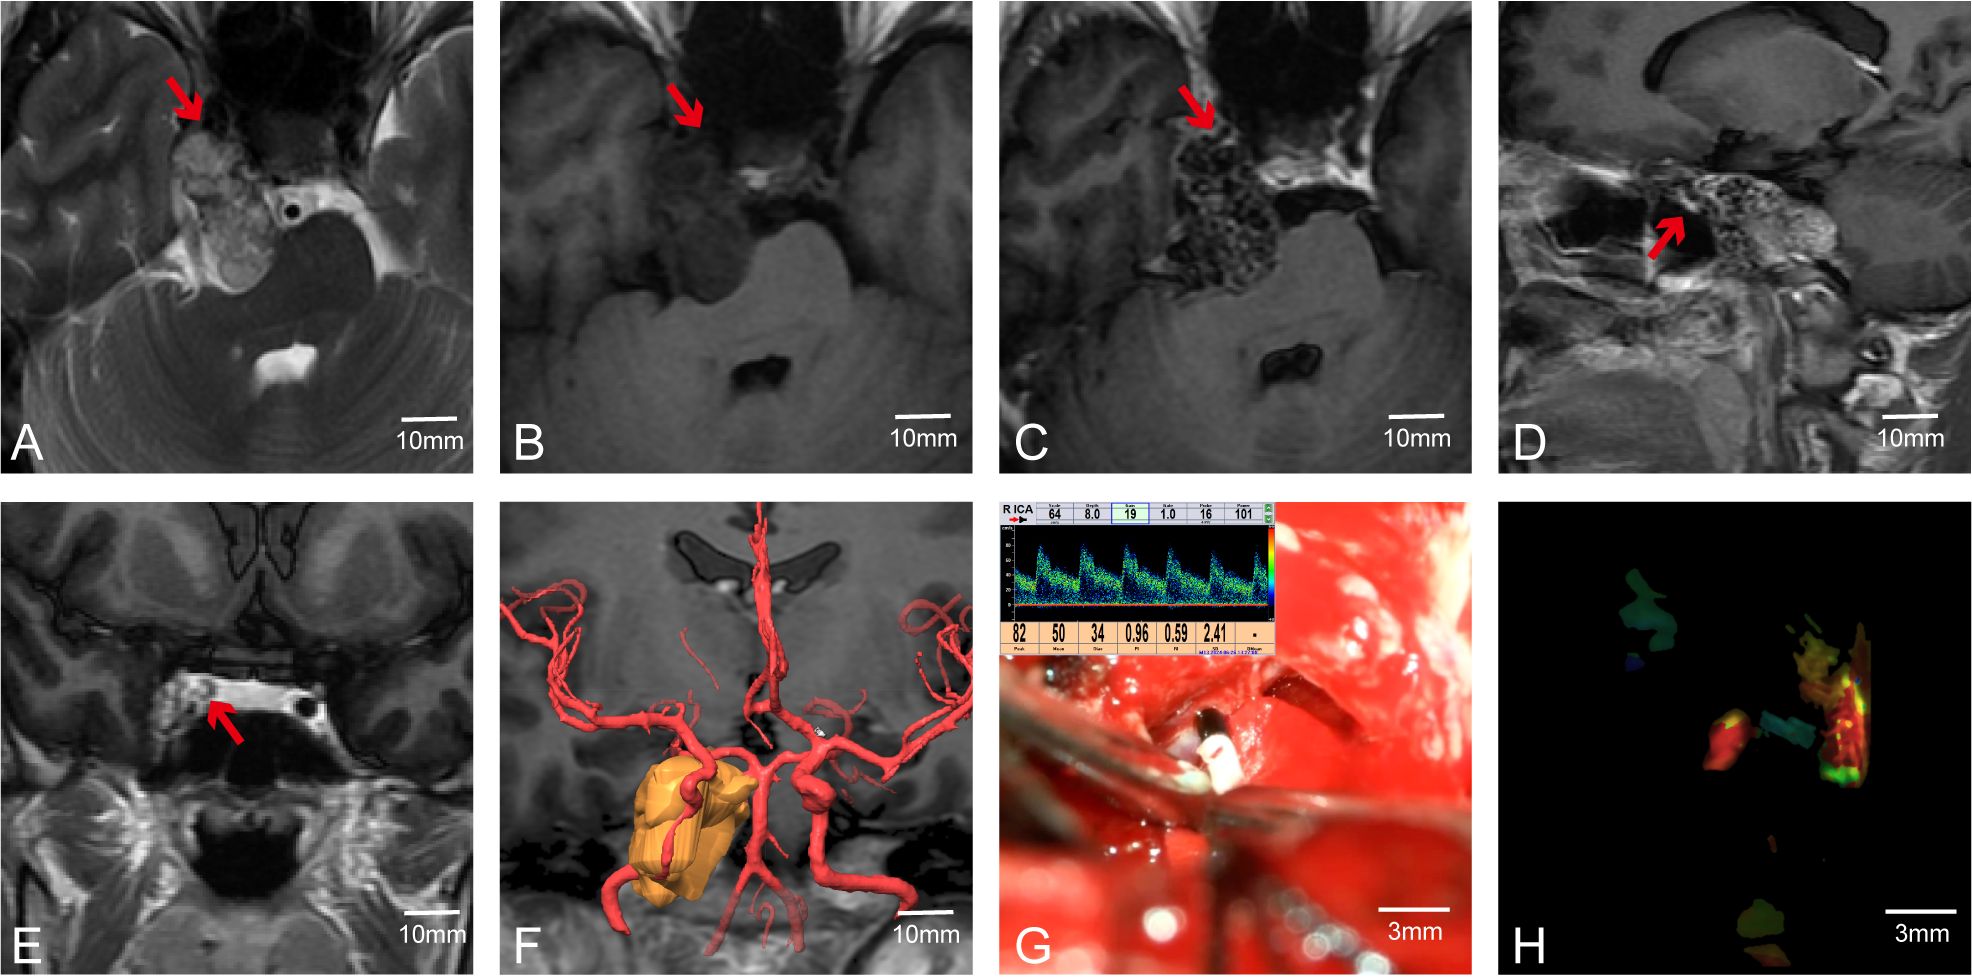

In addition to using MVD to determine the position (anatomical location) and course (spatial trajectory and direction) of arteries—particularly important in skull base tumors where vessels like the internal carotid artery (ICA) may be displaced or encased—we also employed FLOW800 fluorescence imaging during surgery. After injecting indocyanine green, FLOW800 technology provides fluorescence imaging of blood vessels to confirm their positions. For instance, in Case 56, the tumor was located in the right cavernous sinus and clivus (Figures 5A–E). Preoperative multimodal fusion showed the ICA located anteroinferior to the tumor and encased by it (Figure 5F). During surgery, we used MVD and FLOW800 to mutually confirm the ICA position (Figures 5G, H). The tumor was completely resected while preserving the blood vessels. MVD can show the direction and flow of blood, while FLOW800 can display the vessel diameter. The combined use of both methods offers better protection of blood vessels.

Figure 5. Case 56. The combined use of MVD and FLOW800 in skull base tumor surgery. (A–E)Preoperative MR showed that the right ICA was anterior to the tumor. (F) Preoperative multimodal fusion. (G, H) The internal carotid artery was detected during the operation and compared with FLOW800.